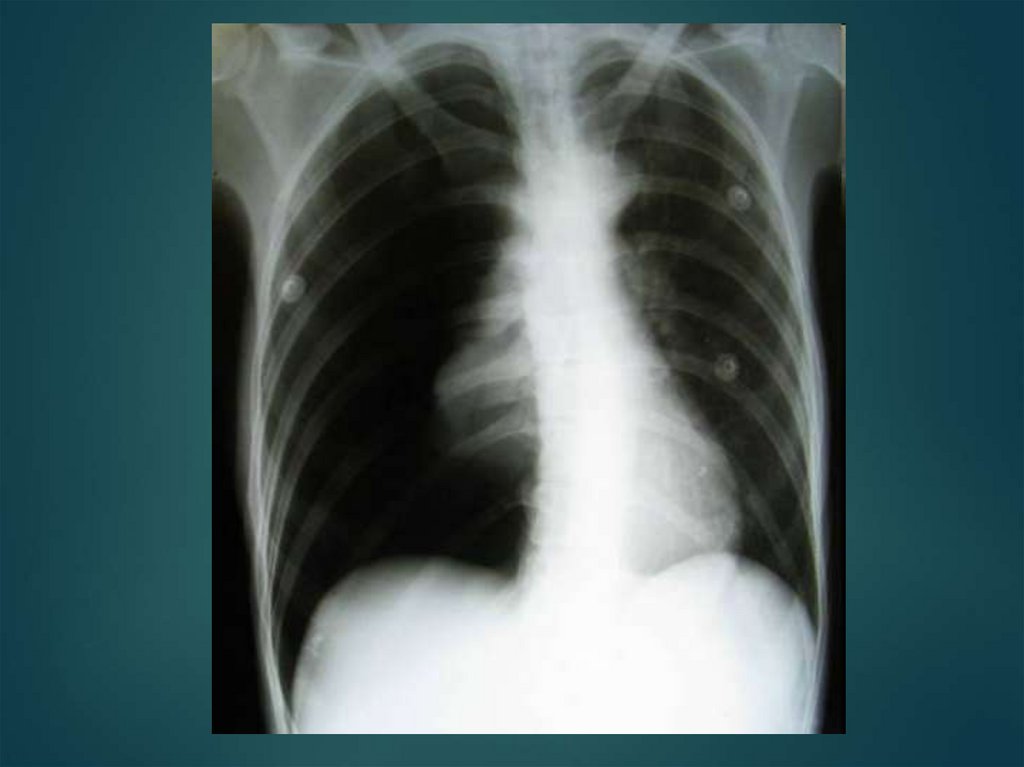

Пневмоторакс-это накопление воздуха в плевральную полость, делится на закрытый, открытый и клапанный.

Пневмоторакс

Закрытый пневмоторакс

Открытый пневмоторакс

Проникающая или открытая травма грудной клетки с образованием пневмоторакса

Клиника

клапанный пневмоторакс

Различают наружный и внутренний клапанный пневмоторакс

Первая помощь

Лечение:

47. Закрытый пневмоторакс

такое состояние,

когда рана грудной

клетки закрывается

сместившимися

тканями, а

поступивший в

плевральную

полость воздух не

сообщается с

внешней средой.

48. Закрытый пневмоторакс

возникает в результате быстрого

кратковременного поступления атмосферного

воздуха в замкнутую плевральную полость, в

момент ранения. Образующиеся вслед за ним

быстрое и плотное соприкосновение

(склеивание) краев раны, смещение мягких

тканей по ходу раневого канала, закупорка их

сгустками крови и т.п. прекращают дальнейшую

возможность поступления воздуха в полость

плевры.

Состояние средней тяжести, бледность кожных

покровов, одышка. При аускультации ослабление

дыхания на стороне поражения. При перкуссии –

коробочный звук в верхних отделах грудной клетки

49. Закрытый пневмоторакс

Небольшое количество воздуха (300—500 см3)

рассасывается в течение 2—3 нед. Если легкое

поджато более чем на 1/4 своего объема,

производят плевральную пункцию для

максимального удаления воздуха.